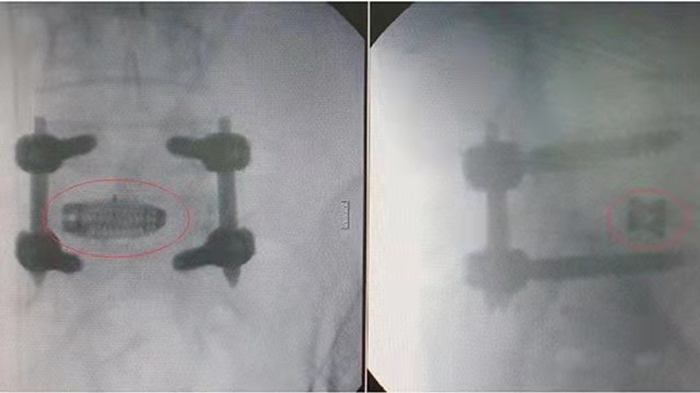

MANTIZ is a medical device company that uses superior engineering and technology to achieve an active and painless life for all patients with spinal disorders. MANTIZ has obtained KFDA certification (medical device approval) and is listed on the HIRA (Health Insurance Review and Evaluation) list in South Korea. MANTIZ began developing 3D-printed cage implants in 2018 with government approval and funding. In May 2019, they launched a 3D-printed PANTHER cage system for PLIF (Poster Lumbar Interbody fusion) / TLIF / OLIF / ALIF surgery. This process uses 3D-printed cage implants without outsourcing the manufacturing process to a third party. This saves customers time and money and reduces the chance of production errors. MANTIZ uses EPLUS 3D's EP-M250 metallic 3D printer to manufacture cages printed in titanium 3D for use in implant surgery. The entire process of shaping the implant is done internally by MANTIZ. The cage is designed according to specifications. Size, material, shape and porosity are essential to the effectiveness of the implant. The complete design of the cage is loaded into the printer software, where it is ready for printing. The large print bed of EP-M250 can be used to print more than 50 individual implants in one structure. Upon transplantation, the bone and surrounding tissue begin to fuse with the implant, creating a strong structure in the patient's spine. Hongwon Yoon (CTO of MANTIZ) the inventor of MANTIZ's PANTHER 3D print cage system, said: "We have completed the development of a more improved titanium 3D printed cage implant using the EP-M250 3D metal printer. Mechanical test results prove the safety and functionality of the implant. 3D printing The average closed pore ratio of the solid titanium component is 3%, which promotes the binding of the protein for bone fusion to the mesenchymal stem cells.”

Through the process of “design-3D printing-post-processing-testing”, the PANTHER can be ready for operating surgery. Currently, the PANTHER has already been applied in treatment for patients.